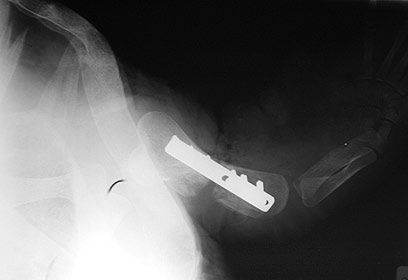

פלטת התמיכה המחברת את עצם הזרוע השבורה (צילום: ד"ר צחי אייזנברג, מרפאת "כל חי")

הווטרינרים מציינים כי מדובר בניתוח ראשון מסוגו שהתקיים בישראל. יוסף שביצע את הניתוח, חיבר את עצם הזרוע שנשברה באמצעות פלטת מתכת והשתיל עצם משריונו הצב כדי למלא את העצם השבורה, דבר שיסייע במלאכת האיחוי.

"הגפה השמאלית שלו נכרתה בעקבות הפציעה, אך סביב הגפה הימנית היה כרוך חוט דיג שגרם לשבר במרכז העצם", אומר ל-ynet הווטרינר ד"ר צחי אייזנברג. "אחרי שניקינו את כל האזור, גילינו שנותר רווח גדול בין שני חלקי העצם, כך שהיינו חייבים להתקין פלטת ברזל שתחזיק את הרווחים ושתל עצם כדי לאחות את הכל. מדובר בפרוצדורות לא שגרתיות".